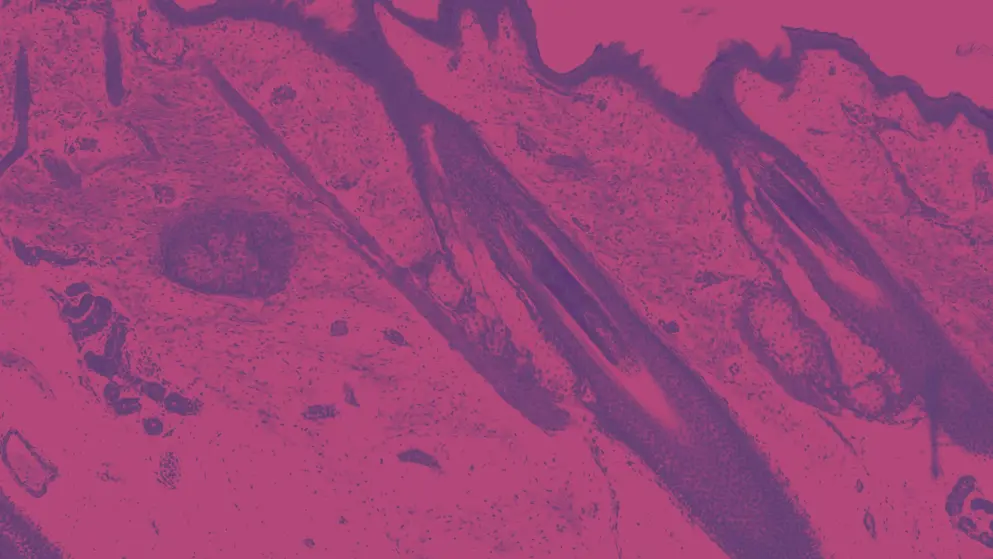

Alopecia areata (AA) exhibits considerable heterogeneity in its clinical presentation. Are you aware how this affects diagnosis, treatment, and patient quality of life?

- Understand diagnostic and severity assessment challenges in SOC patients, and review the best practices for diagnosing and managing AA in these patient populations